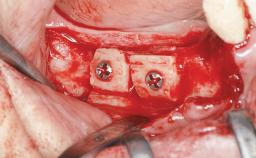

It is well known to clinicians that any removal of teeth will, over time, cause the dimensions of the alveolar ridge to be reduced by resorption of the bundle bone and by changes related to external modeling. This development is particularly evident in the crestal region with its thin buccal bone that consists of bundle bone almost entirely. The facial bone will rapidly resorb as blood supply from the periodontal ligament gets disrupted (Araújo and Lindhe 2005). There is no reason why traumatic tooth loss should not have the same consequences. It takes more than achieving implant osseointegration for a treatment outcome to be considered successful. No deficiency of bone or soft tissue is acceptable when an ideal esthetic outcome is the goal. Several articles (Sanz and coworkers 2011; Vignoletti and coworkers 2011) have reported on techniques of improving the alveolar ridge for implant treatment, notably focusing on protecting tissues from resorption.